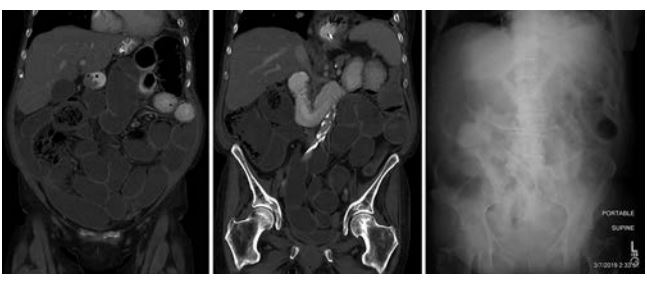

美国哈佛大学的RobertJ Besaw教授报道过1例接受PD-1抗体治疗后出现慢性肠梗阻的病人。

病人反复出现肠梗阻的症状,但是反复CT检查发现肠子是通畅的,也没有看到炎症反应、肠道感染等,因此怀疑是PD-1抗体导致的假性肠梗阻。激素治疗后有所好转,然后就开始全肠外营养支持。此后,患者病情稳定。

这个案例提醒我们:接受免疫治疗的患者,如果无缘无故地出现肠梗阻的症状,经CT、X线等检查排除了肠梗阻,“事出蹊跷,必有妖”,这时候别忘了可能是PD-1抗体导致的假性肠梗阻。